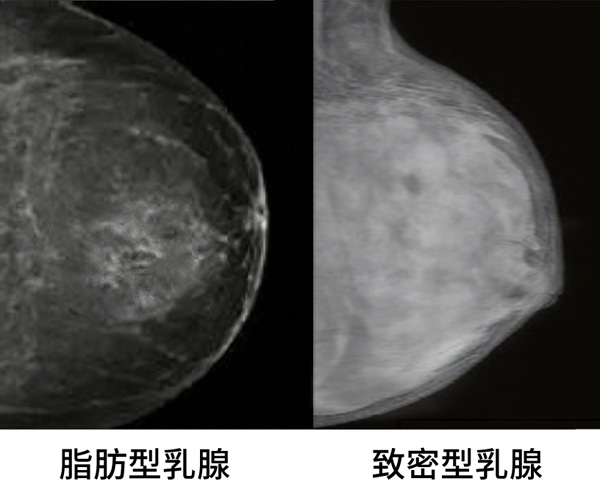

在钼靶成像中:

而致密性乳腺的核心特征,正是腺体组织占比高,背景本身就是“白的”。

结果是:肿瘤与背景在灰阶上高度重叠,对比度被系统性抹平。哪怕是经验丰富的放射科医生,也只能在“白上找白”。

但这套体系有一个前提:大多数受检人群是脂肪型或中等密度乳腺。一旦进入致密性乳腺占比极高的人群,钼靶在物理成像层面就开始系统性失效。